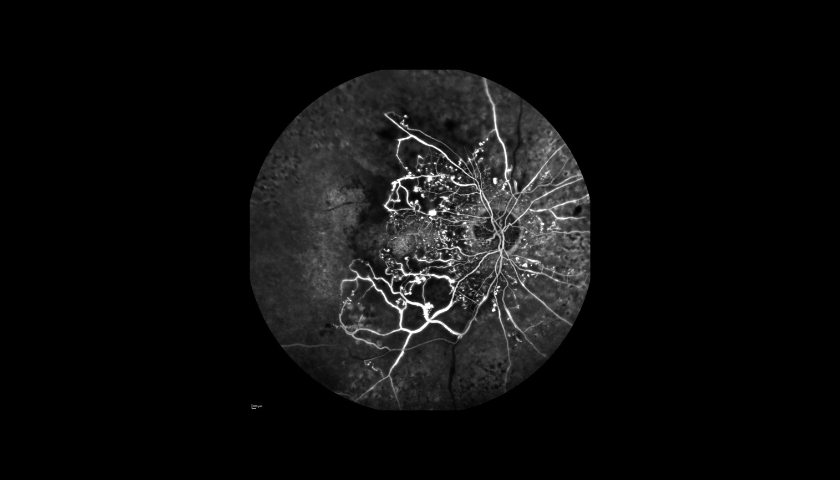

A Angiografia Fluoresceínica (AF) é um exame auxiliar de diagnóstico e monitorização em oftalmologia que permite visualizar e analisar a circulação da retina, com o objetivo de identificar possíveis alterações ou lesões que expliquem um determinado quadro clínico.

A Angiografia é indicada principalmente em patologias como a Retinopatia Diabética (RD), a Degenerescência da Idade (DMI), as oclusões vasculares (tromboses) e os tumores oculares. Utilizando o Spectralis® HRA+OCT (com as lentes de 30o, 55o ou 102o), é um procedimento de diagnóstico no qual uma sequência rápida de fotografias é tirada após injeção de um corante para documentar a circulação sanguínea da Retina e também da Coróide e assim ajudar a diagnosticar e tratar muitas doenças oculares.